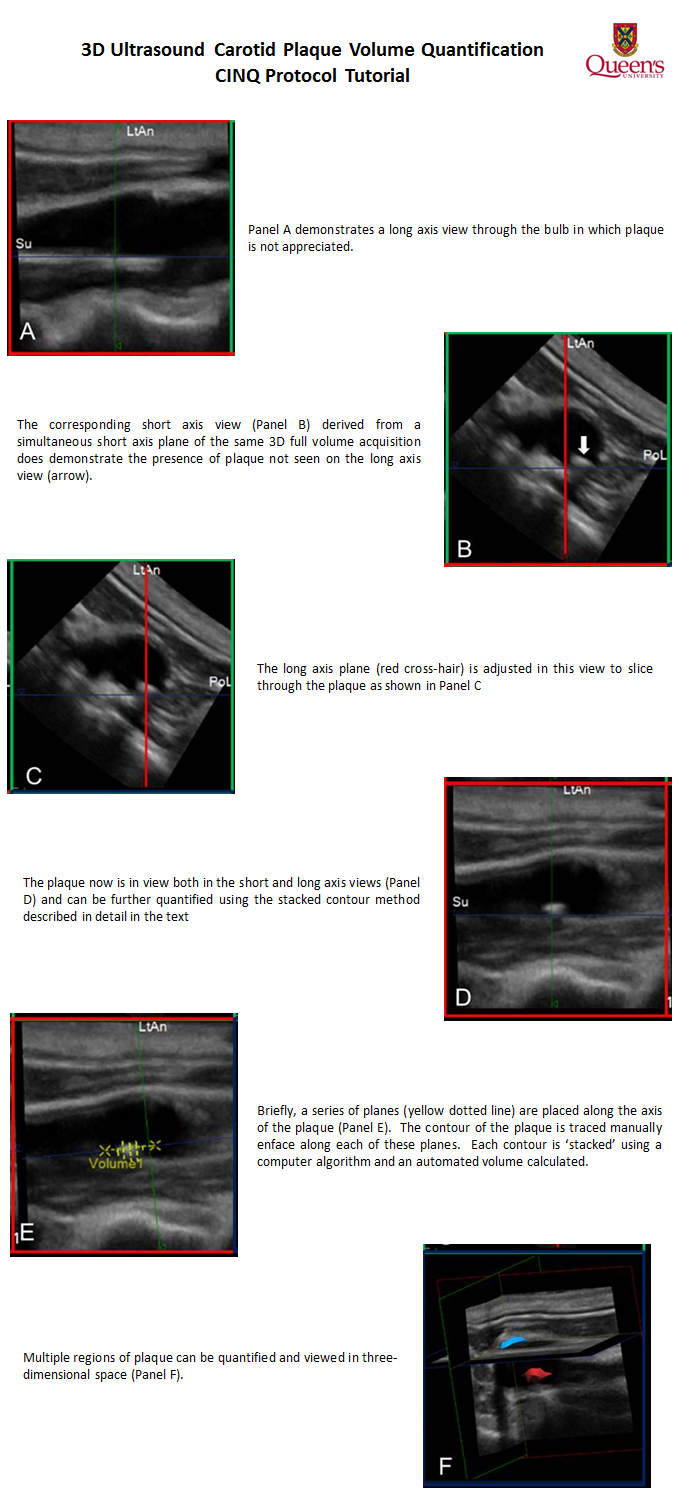

Johri AM, Chitty D, Malik P, Matangi M, Malik P, Mousavi P, Day A, Simpson C. (2013). Can Carotid Bulb Plaque Assessment Rule out Significant Coronary Artery Disease? A Comparison of Plaque Quantification by Two- and Three-dimensional Ultrasound. J Am Soc Echocardiogr, 26(1):86-95.